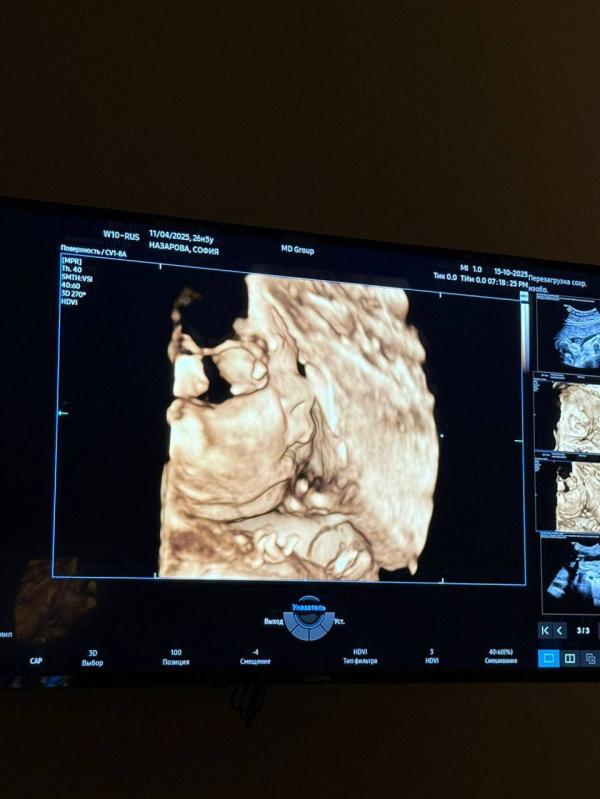

У меня сегодня 27,5 недель по первому скринингу, вес малышки 930 грамм, врач говорит маловато, что худенькая будет. Может у кого было так же, с каким весом родили ?

Тоже вчера была на узи 26 недель, вес 739 грамм, сказали тоже маленькая( переживаю